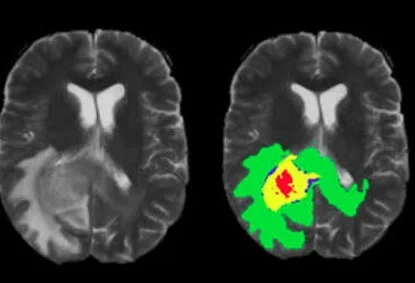

Both image annotation and segmentation services are integral to medical image analysis, contributing to the development of AI-powered tools, clinical decision support systems, and research outcomes.

Outsourcing image annotation services allows organizations to access the expertise of professionals who are well-versed in medical imaging. Image annotation companies often employ radiologists, medical professionals, and imaging experts who have extensive training in medical image analysis. This ensures that the annotated data is of the highest quality, which is essential for AI training, clinical decision-making, and research purposes.

Moreover, outsourcing companies invest heavily in advanced image annotation tools and AI-assisted platforms, which are costly for individual organizations to implement on their own. These tools enhance the accuracy of segmentation and annotation, ensuring precise results that may not be achievable with manual processes.

Medical image annotation and segmentation are crucial to the development of AI-based diagnostic tools and for clinical research. Any mistakes in annotation can lead to inaccurate machine learning models or flawed research findings. Hence, accuracy is paramount.

Reputable image annotation companies adhere to strict quality control measures to ensure that the annotations they provide are accurate and reliable. These companies implement multiple layers of quality checks, including manual reviews and automated validation systems, to minimize the risk of errors. As a result, outsourcing to established companies often results in more accurate and precise annotations compared to relying on in-house teams with less experience or expertise.

Moreover, outsourcing allows for access to specialized tools and technologies that can improve the consistency and accuracy of image annotations, leading to higher-quality data for AI model training, clinical analysis, and research.